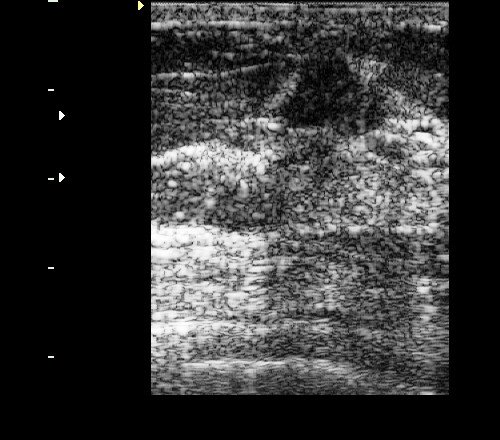

Рис. 5. Фиброаденомы молочной железы: овальные гипоэхогенные горизонтально ориентированные неоднородные образования с четкими мелкобугристыми контурами.